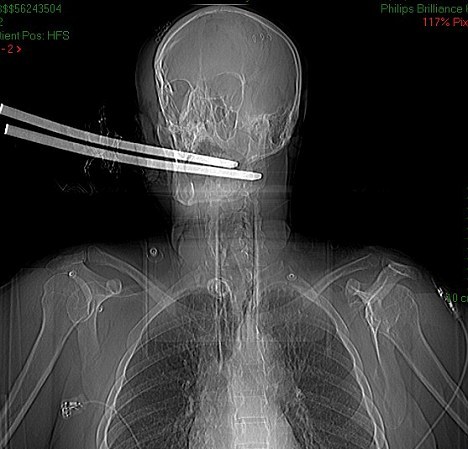

Ο Hugh έπεσε λιπόθυμος στο πάτωμα μέσα σε μια λίμνη αίματος. Τον βρήκαν την επόμενη μέρα και όταν μεταφέρθηκε στο νοσοκομείο οι γιατροί αναγκάστηκαν να καλέσουν την πυροσβεστική για να κόψουν με ειδικά εργαλεία τα «δόντια» που «περίσσευαν», ενώ είχαν προειδοποιήσει την οικογένειά του ότι δε θα άντεχε περισσότερες από 24 ώρες.

Επί τρεις μήνες ήταν σε κώμα και πάλευε για τη ζωή του και τελικά τα κατάφερε. Όμως η ζωή του ποτέ δε θα είναι ξανά φυσιολογική, καθώς χρειάζεται καθημερινή φροντίδα από ειδικό νοσηλευτή, λόγω των βαρύτατων εγκεφαλικών κακώσεων που υπέστη ενώ έχει χάσει και την ικανότητα της ομιλίας.